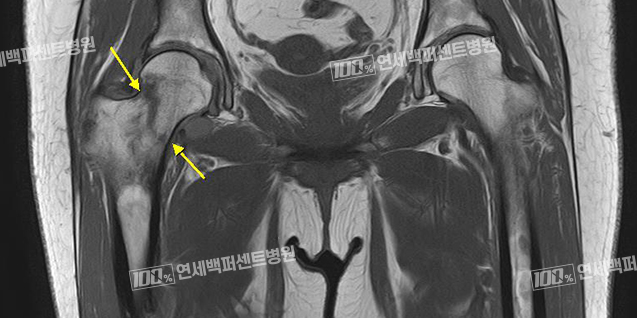

고관절 골절 정복 및 내고정술

전자간 골절, 전위가 없는 급성 대퇴경부골절의 경우에는 골절 부위를 나사와 금속판 또는 골수정을 이용하여 고정하는 수술을 합니다.

부러진 뼈가 완전히 붙기까지는 보통 2~3개월 정도 소요되며 뼈가 완전히 붙을 때까지 과도한 운동을 삼가하고 안정을 취해야 합니다.

대퇴골 전자간 골절 수술 전

대퇴 골수정 고정술 후

전위없는 급성 대퇴경부 골절 수술전

다발성 금속 나사 고정술 후